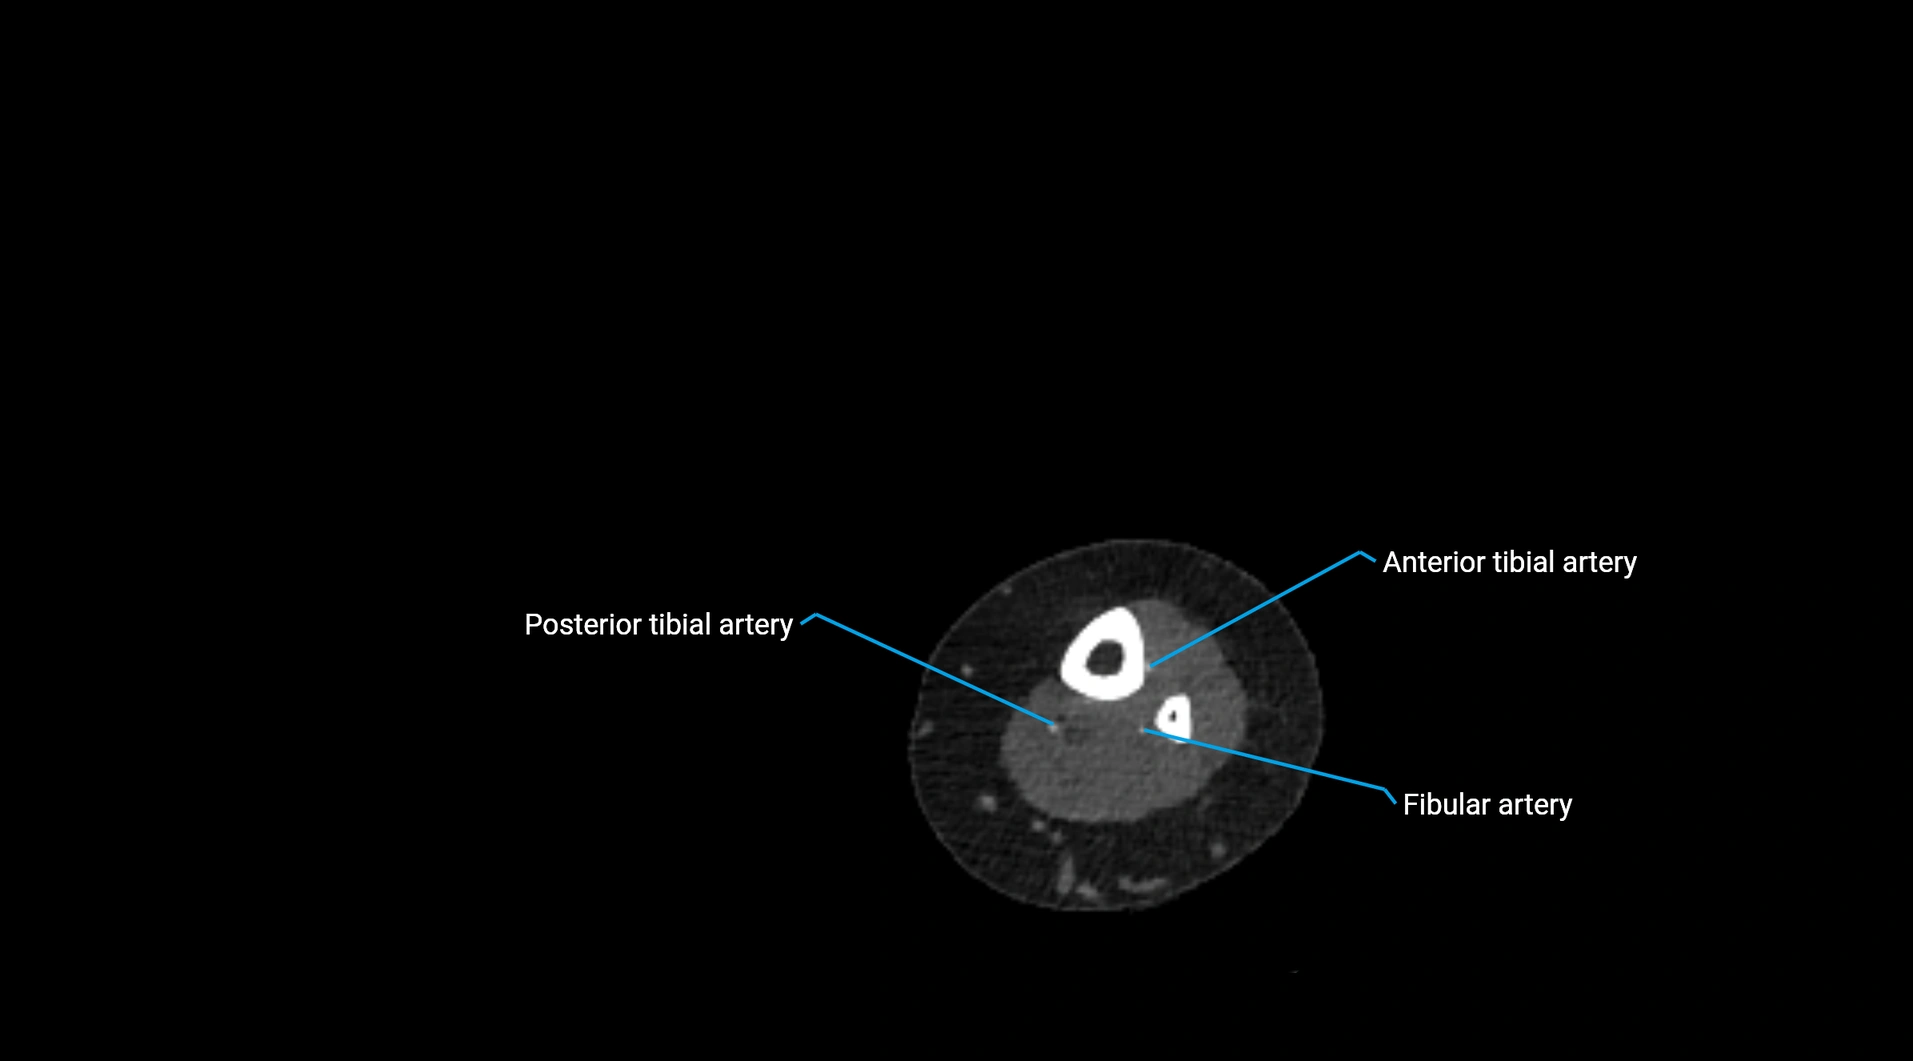

Contrast-enhanced CT (CTA):

• Gold standard for abdominal aortic imaging

• Provides excellent detail of lumen, wall, aneurysm, thrombus, and branch vessels

• Multiplanar and 3D reconstructions help in aneurysm measurement, stent graft planning, and dissection evaluation

• Detects acute rupture, traumatic injury, or occlusion with high sensitivity